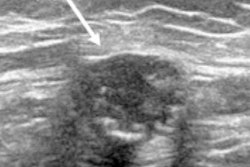

Ultrasonography of the left axilla shows an enlarged 17 mm reactive lymph node in a 45-year-old woman about a week after receiving the firrst dose of the Vaxzevria COVID-19 vaccine (Astra Zeneca). Note the asymmetrical cortical thickening (white arrow) associated with a well-represented central fatty hilum. All images courtesy of the EUSOBI and Insights into Imaging.In the article, the EUSOBI group provides 10 recommendations about general issues (numbers 1 and 2 below); asymptomatic subjects, including women attending screening programs (number 3); cases with symptoms or imaging-detected findings (number 4-9); and complex cases (number 10):